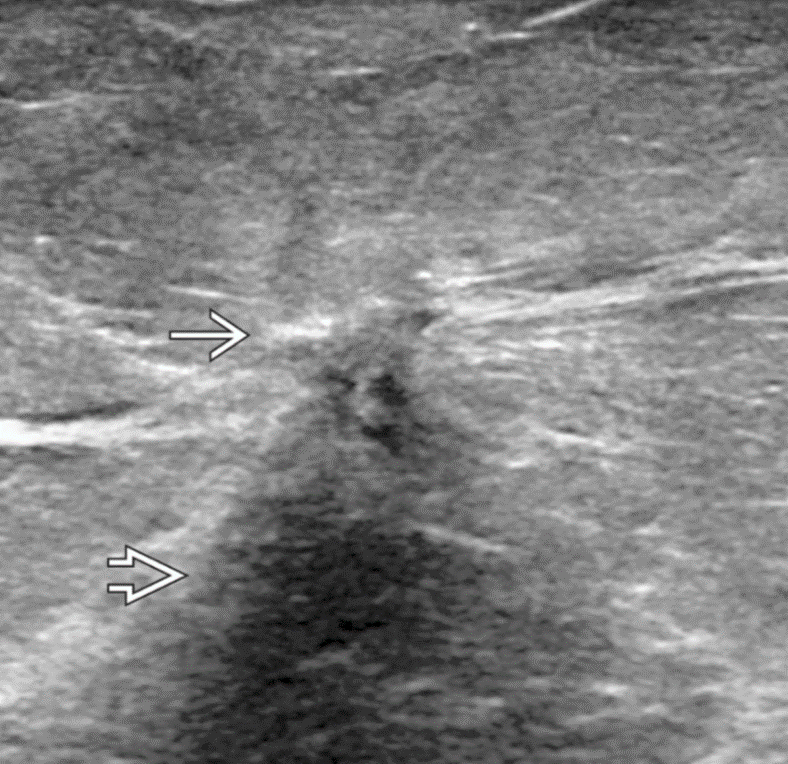

US: Irregular, spiculated mass with indistinct margins

Medullary or tubular IDC?

More likely medullar bacause it is mass forming. Tubular is spiculated